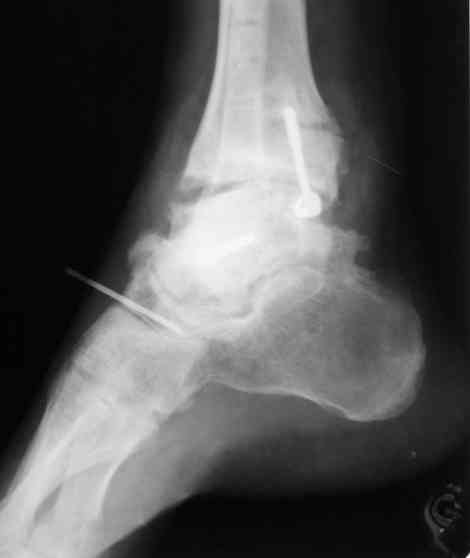

Имя     : после опер.jpg

Тип     : image/jpeg

Размер  : 18969 байтов

Описание: отсутствует

Url     : http://weborto.net:8080/pipermail/ortho/attachments/20070616/4aa8531d/attachment-0008.jpg

В Вашей ситуации мы произвели открытую репозицию и фиксацию

металлоконструкциями. Все зажило первично, посттравматического

дефартроза избежать не удалось. Пациент от артродезирующих операций в

отдаленном периоде отказался.